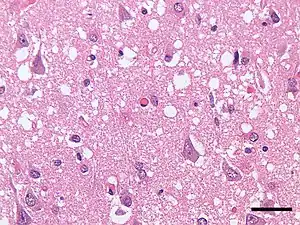

| Micrograph showing spongiform degeneration (vacuoles that appear as holes in tissue sections) in the cerebral cortex of a patient who had died of a prion disease (Creutzfeldt-Jakob disease). H&E stain. Scale bar = 30 microns (0.03 mm). | |

Prions cause neurodegenerative disease by aggregating extracellularly within the central nervous system to form plaques known as amyloids, which disrupt the normal tissue structure. This disruption is characterized by "holes" in the tissue with resultant spongy architecture due to the vacuole formation in the neurons.[66] Other histological changes include astrogliosis and the absence of an inflammatory reaction.[67] While the incubation period for prion diseases is relatively long (5 to 20 years), once symptoms appear the disease progresses rapidly, leading to brain damage and death.[68] Neurodegenerative symptoms can include convulsions, dementia, ataxia (balance and coordination dysfunction), and behavioural or personality changes.